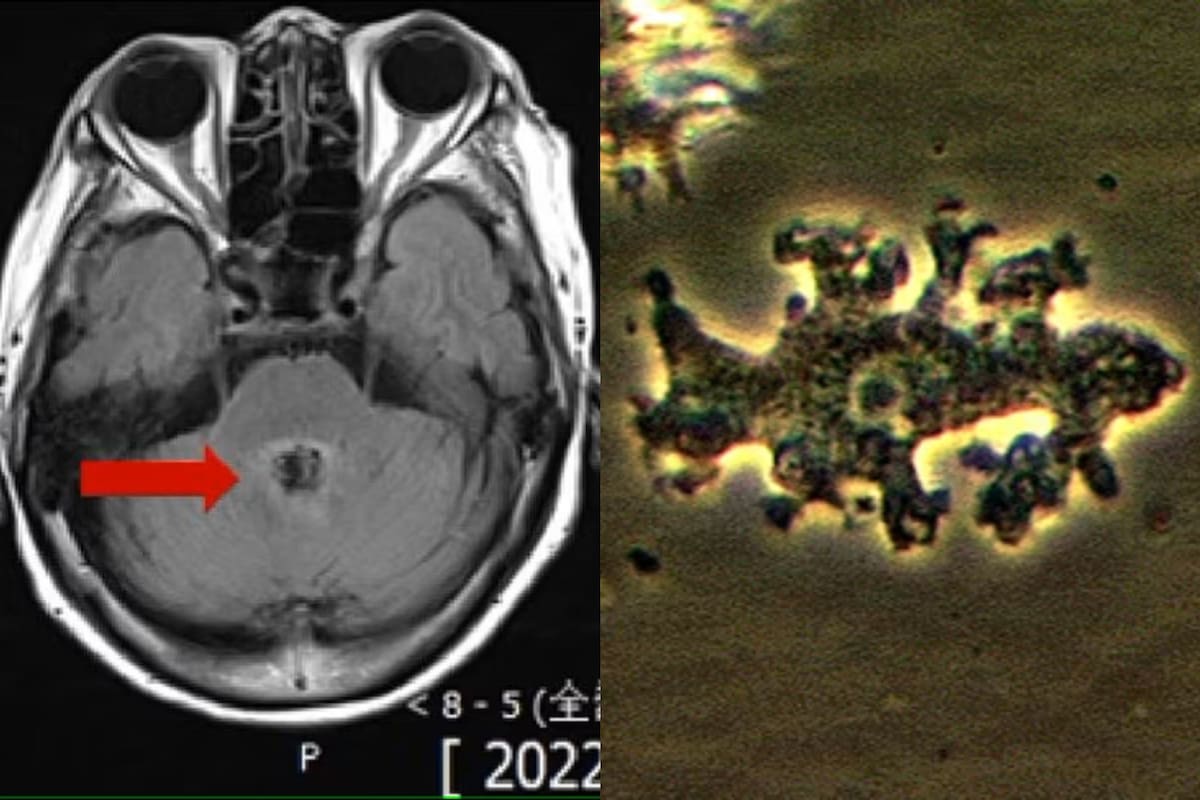

Hace días se convirtió en viral la historia de una mujer que puso en alerta a las comunidades rurales por un parásito potencialmente letal que ingresaría al cuerpo humano, se instalaría en el cerebro y produciría una muerte dolorosa. La paciente, de origen chino cuyo nombre se mantuvo en el anonimato, murió luego de que los médicos confundieran un tumor en su cabeza con una “ameba come cerebros”.

Según detalló el medio citado, la mujer asistió al hospital porque tenía dolor de cabeza, mareos, confusión y dificultad para hablar. En un estudio preliminar por resonancia, los médicos determinaron que tenía cáncer, en particular por la lesión en el cerebro que era evidente. Sin embargo, a los pocos días le realizaron una punción lumbar -para extraer líquido necesario para analizar- y el resultado fue mucho más angustiante.

La mujer estaba infectada con la ameba Balamuthia mandrillaris, que se instala en el cerebro y se alimenta de este. El nombre propio de la enfermedad se denomina encefalitis granulomatosa amebiana y cuatro tipos de ellas pueden ser letales.